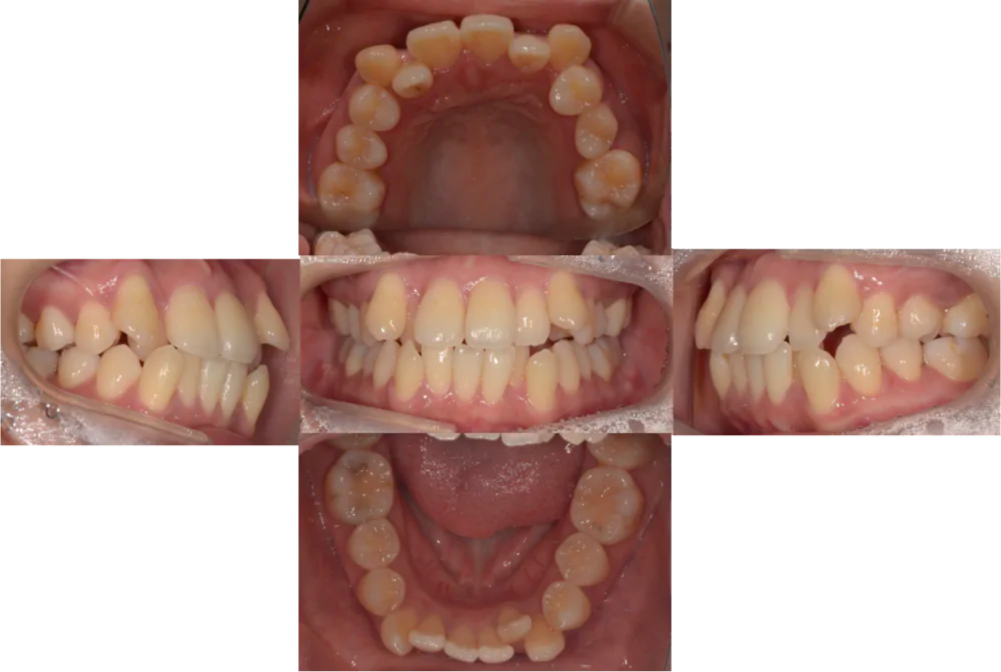

初診時

動的治療終了時

Before・after

| 主訴 | 八重歯があり、口元の突出感が気になる |

|---|---|

| 矯正装置 | インビザラインシステム、エラスティックゴム、リンガルボタン(クリア) |

| 初診時年齢 | 29歳 |

| 診断 | 叢生および上下歯性前突を伴う両側AngleClass1、SkeletalClass |

| 抜歯の有無 | 上下左右第一小臼歯抜歯 |

| 来院頻度 | 4〜8週間に1回 |

| 治療期間 | 24ヶ月 |

| 費用の目安 | 80万円程度 |

| リスク | ・歯を並べるために抜歯が必要になる ・装置が擦れて唇や頬に口内炎ができることがある ・マウスピース装着時間を遵守しないと治療効果が得られない可能性がある ・エラスティックゴムを指定時間使用しないと治療効果が得られないことがある ・歯根吸収を誘発する可能性があ |